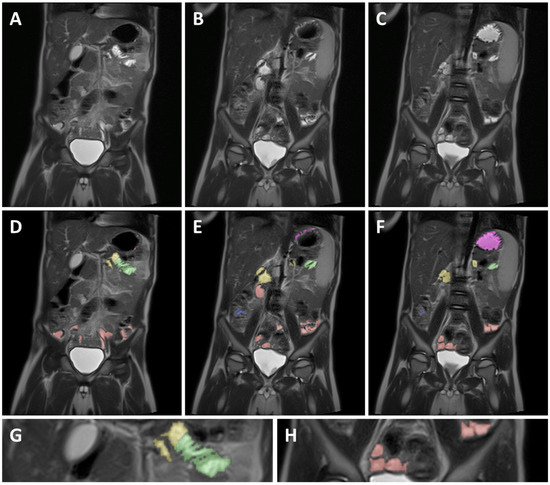

To ensure consistency, different GI segments were identified based on the following identification criteria for each segment. Identifications of the different GI segments are described from the patient’s perspective. An example can be found in Figure 2.

2.4.1. Stomach

When dividing the body using an X, Y coronal plane, the stomach is located in the top left quadrant and passes over the Y-axis to the top right quadrant. Due to the presence of often larger and localized fluid volumes, it is relatively easy to identify the stomach and integrate the fluid volume. The pylorus was identified as the end of the stomach and served as a marker for the start of the duodenum.

2.4.2. Duodenum

The duodenum starts at the duodenal bulb immediately after the pylorus and then typically follows a path down, after which the duodenum crosses the Y-axis of the coronal plane and continues up again until the ligament of Treitz. The ligament of Treitz, and thus the end of the duodenum, was identified as being roughly the same height as the duodenal bulb but on the left side of the spine [27].

2.4.3. Jejunum

As commonly accepted, the jejunum starts at the ligament of Treitz [27]. The end of the jejunum and transition to the ileum, however, is hard to define precisely using MRI imaging [27]. Consequently, the morphology and relative position in the abdominal cavity was used to differentiate between the jejunum and ileum. Morphological differentiation was based on the valvulae conniventes. Due to the closely spaced circular folds and the consequently thicker intestinal wall, the jejunum can be identified by a typical striped pattern in the GI fluid [27] (Figure 2G). In addition, the jejunum is mainly located in the top left quadrant, sometimes extending into the bottom left quadrant of the abdomen, while the ileum is mainly located in the bottom right quadrant, sometimes extending into the bottom left quadrant.

2.4.4. Ileum

Contrary to the jejunum, the ileum has less closely spaced circular folds [27] (Figure 2H). Consequently, the ileum can be identified by a smoother lined and thinner intestinal wall compared to the jejunum. The ileum ends with the ileocecal valve located at the start of the well-defined and easily localized colon.

2.4.5. Colon

The colon is the last part of the GI tract and has a larger diameter as compared to the jejunum and ileum. Additionally, the position of the colon is more fixed [27], therefore allowing for easier identification and localization. The colon follows a well-defined path starting after the ileocecal valve in the lower right quadrant (caecum) and going up (ascending colon). Next, the colon crosses the central Y-axis (transverse colon), after which it comes back down (descending colon) to end as the sigmoid and rectum.

Figure 2. Example of MRI identification of fluid pockets in different GI segments on 3 coronal T2 weighted spin echo images of a 5-year-old child. (AC) are unmarked images; (DF) are the corresponding marked images. Purple marked areas are located in the stomach, yellow in the duodenum, green in the jejunum, red in the ileum, and blue in the colon. (G) is a detailed view of the jejunum (green), showing the circular folds as the typical striped pattern in the fluid pocket. (H) is a detailed view of the ileum marked in red, showing the smooth intestinal wall.